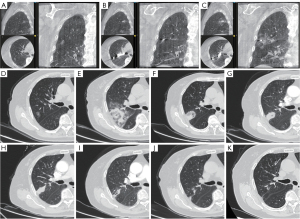

A representative case of CBCT-guided transbronchial RFA is shown in Figure 2. CBCT enabled precise RFA catheter placement, real-time safety assessment, and visualization of ablation zone. The lesion, initially appearing as ground-glass opacity, evolved into fibrotic scar with gradual size reduction; cavitation and fibrosis were occasionally observed.